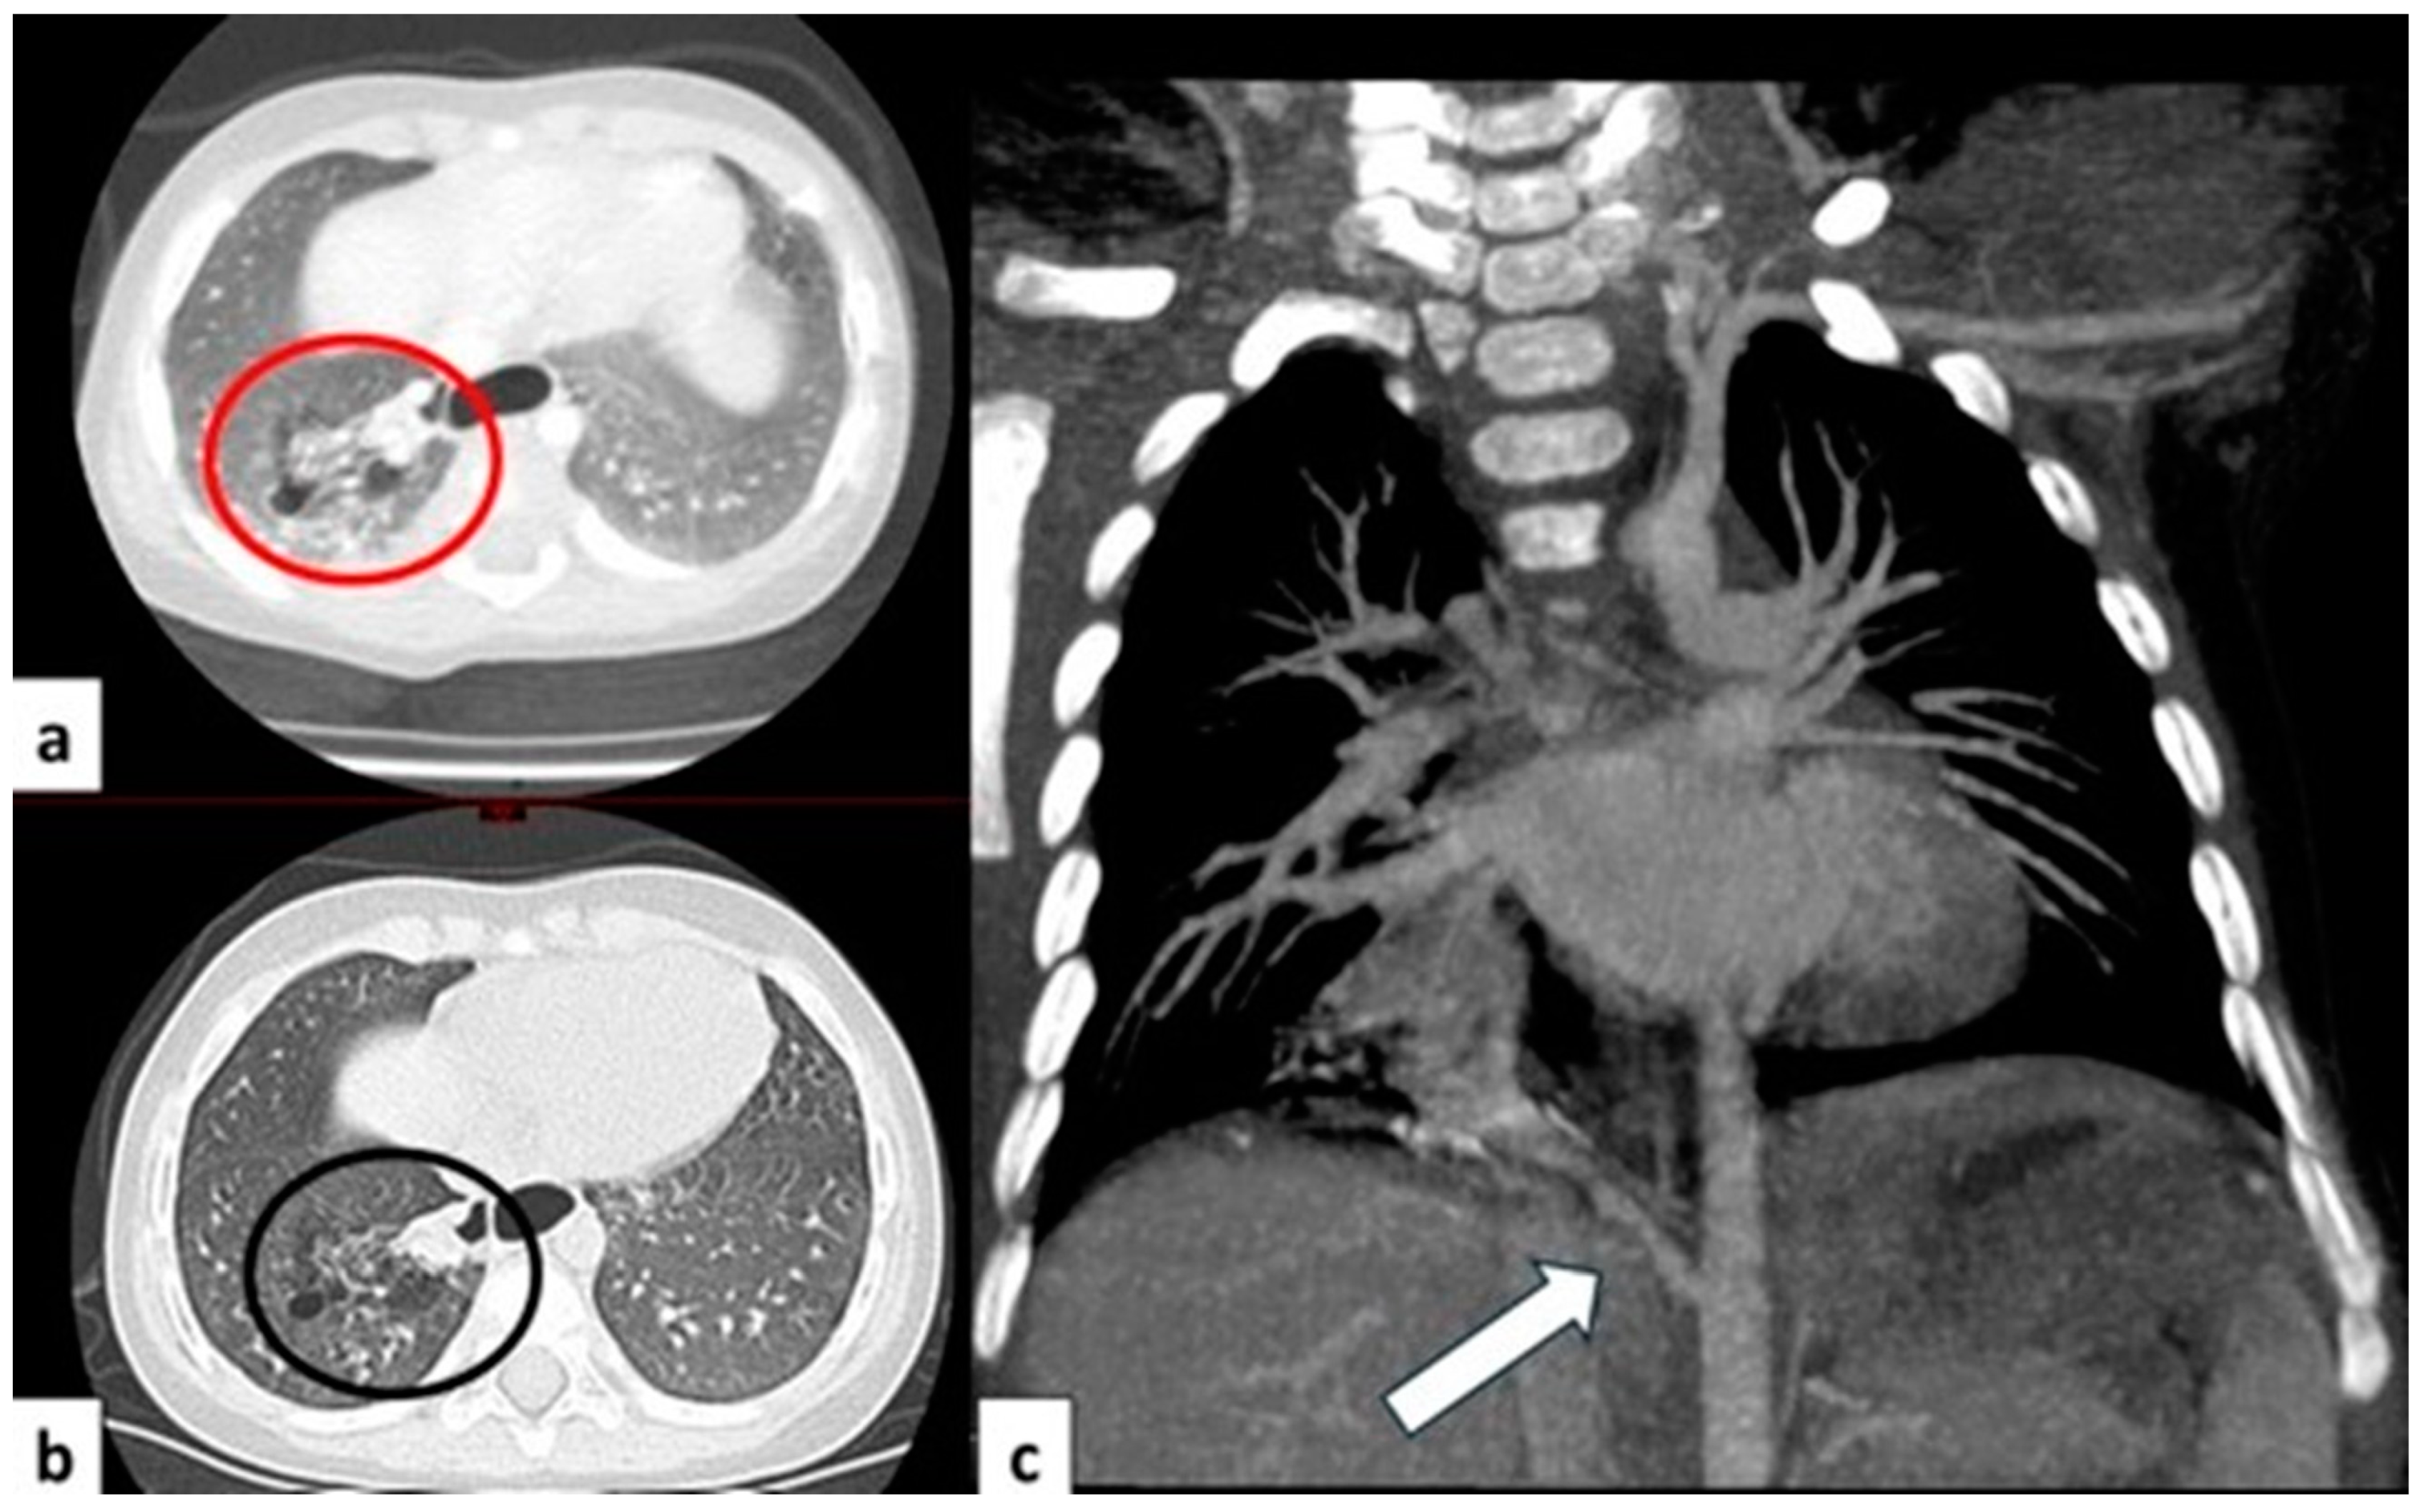

Figure 8.

CT axial image visualized on lung window (a) of a 9 month old boy with right cystic lesions (previously seen on fetal ultrasound) shows an area of parenchymal consolidation mixed with air-filled cystic lesions, located in the right lower lobe (red circle). Contrast-enhanced acquisitions (c) demonstrate an abnormal arterial supply from systemic circulation into sequestered lung (arrow). These findings are compatible with hybrid lesion (CPAM and pulmonary sequestration). A CT scan performed after the arterial embolization of the aberrant vessel (b) shows a mild reduction in sequestered lung parenchyma (black circle).

Figure 9.

CT image of a 4 month old girl presenting with multiple right cystic lesions <2 cm (a) compatible with CPAM type 2. Parenchymal consolidation (b) associated with the aberrant arterial (c) supply from the celiac trunk (red circle) and venous drainage into the pulmonary venous system, further evaluated with the coronal MiP reconstruction, represent a pulmonary intra-lobar sequestration. The combination of these findings supports the diagnosis of a hybrid lesion.